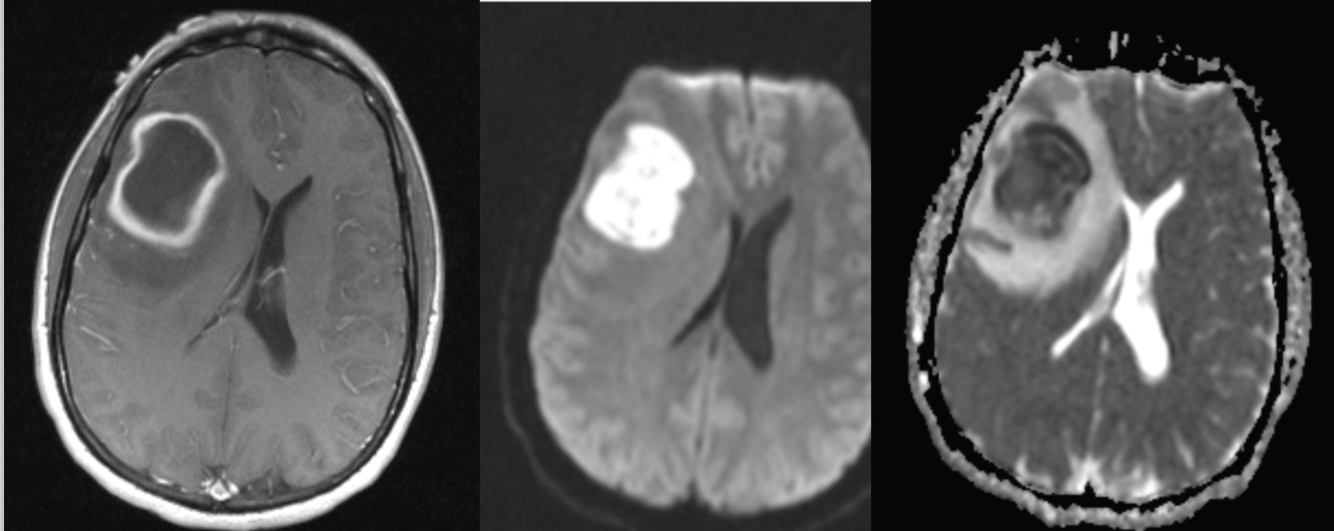

A 54 year-old man presented with headaches and weakness on his left side.

Abscess

Imaging